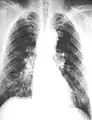

The abnormal chest x-ray and its interpretation remain the most important factors in establishing the presence of pulmonary fibrosis.[11] The findings usually appear as small, irregular parenchymal opacities, primarily in the lung bases. Using the ILO Classification system, "s", "t", and/or "u" opacities predominate. CT or high-resolution CT (HRCT) are more sensitive than plain radiography at detecting pulmonary fibrosis (as well as any underlying pleural changes). More than 50% of people affected with asbestosis develop plaques in the parietal pleura, the space between the chest wall and lungs. Once apparent, the radiographic findings in asbestosis may slowly progress or remain static, even in the absence of further asbestos exposure.[23] Rapid progression suggests an alternative diagnosis.

61 yr old working industrially with asbestos for decades.